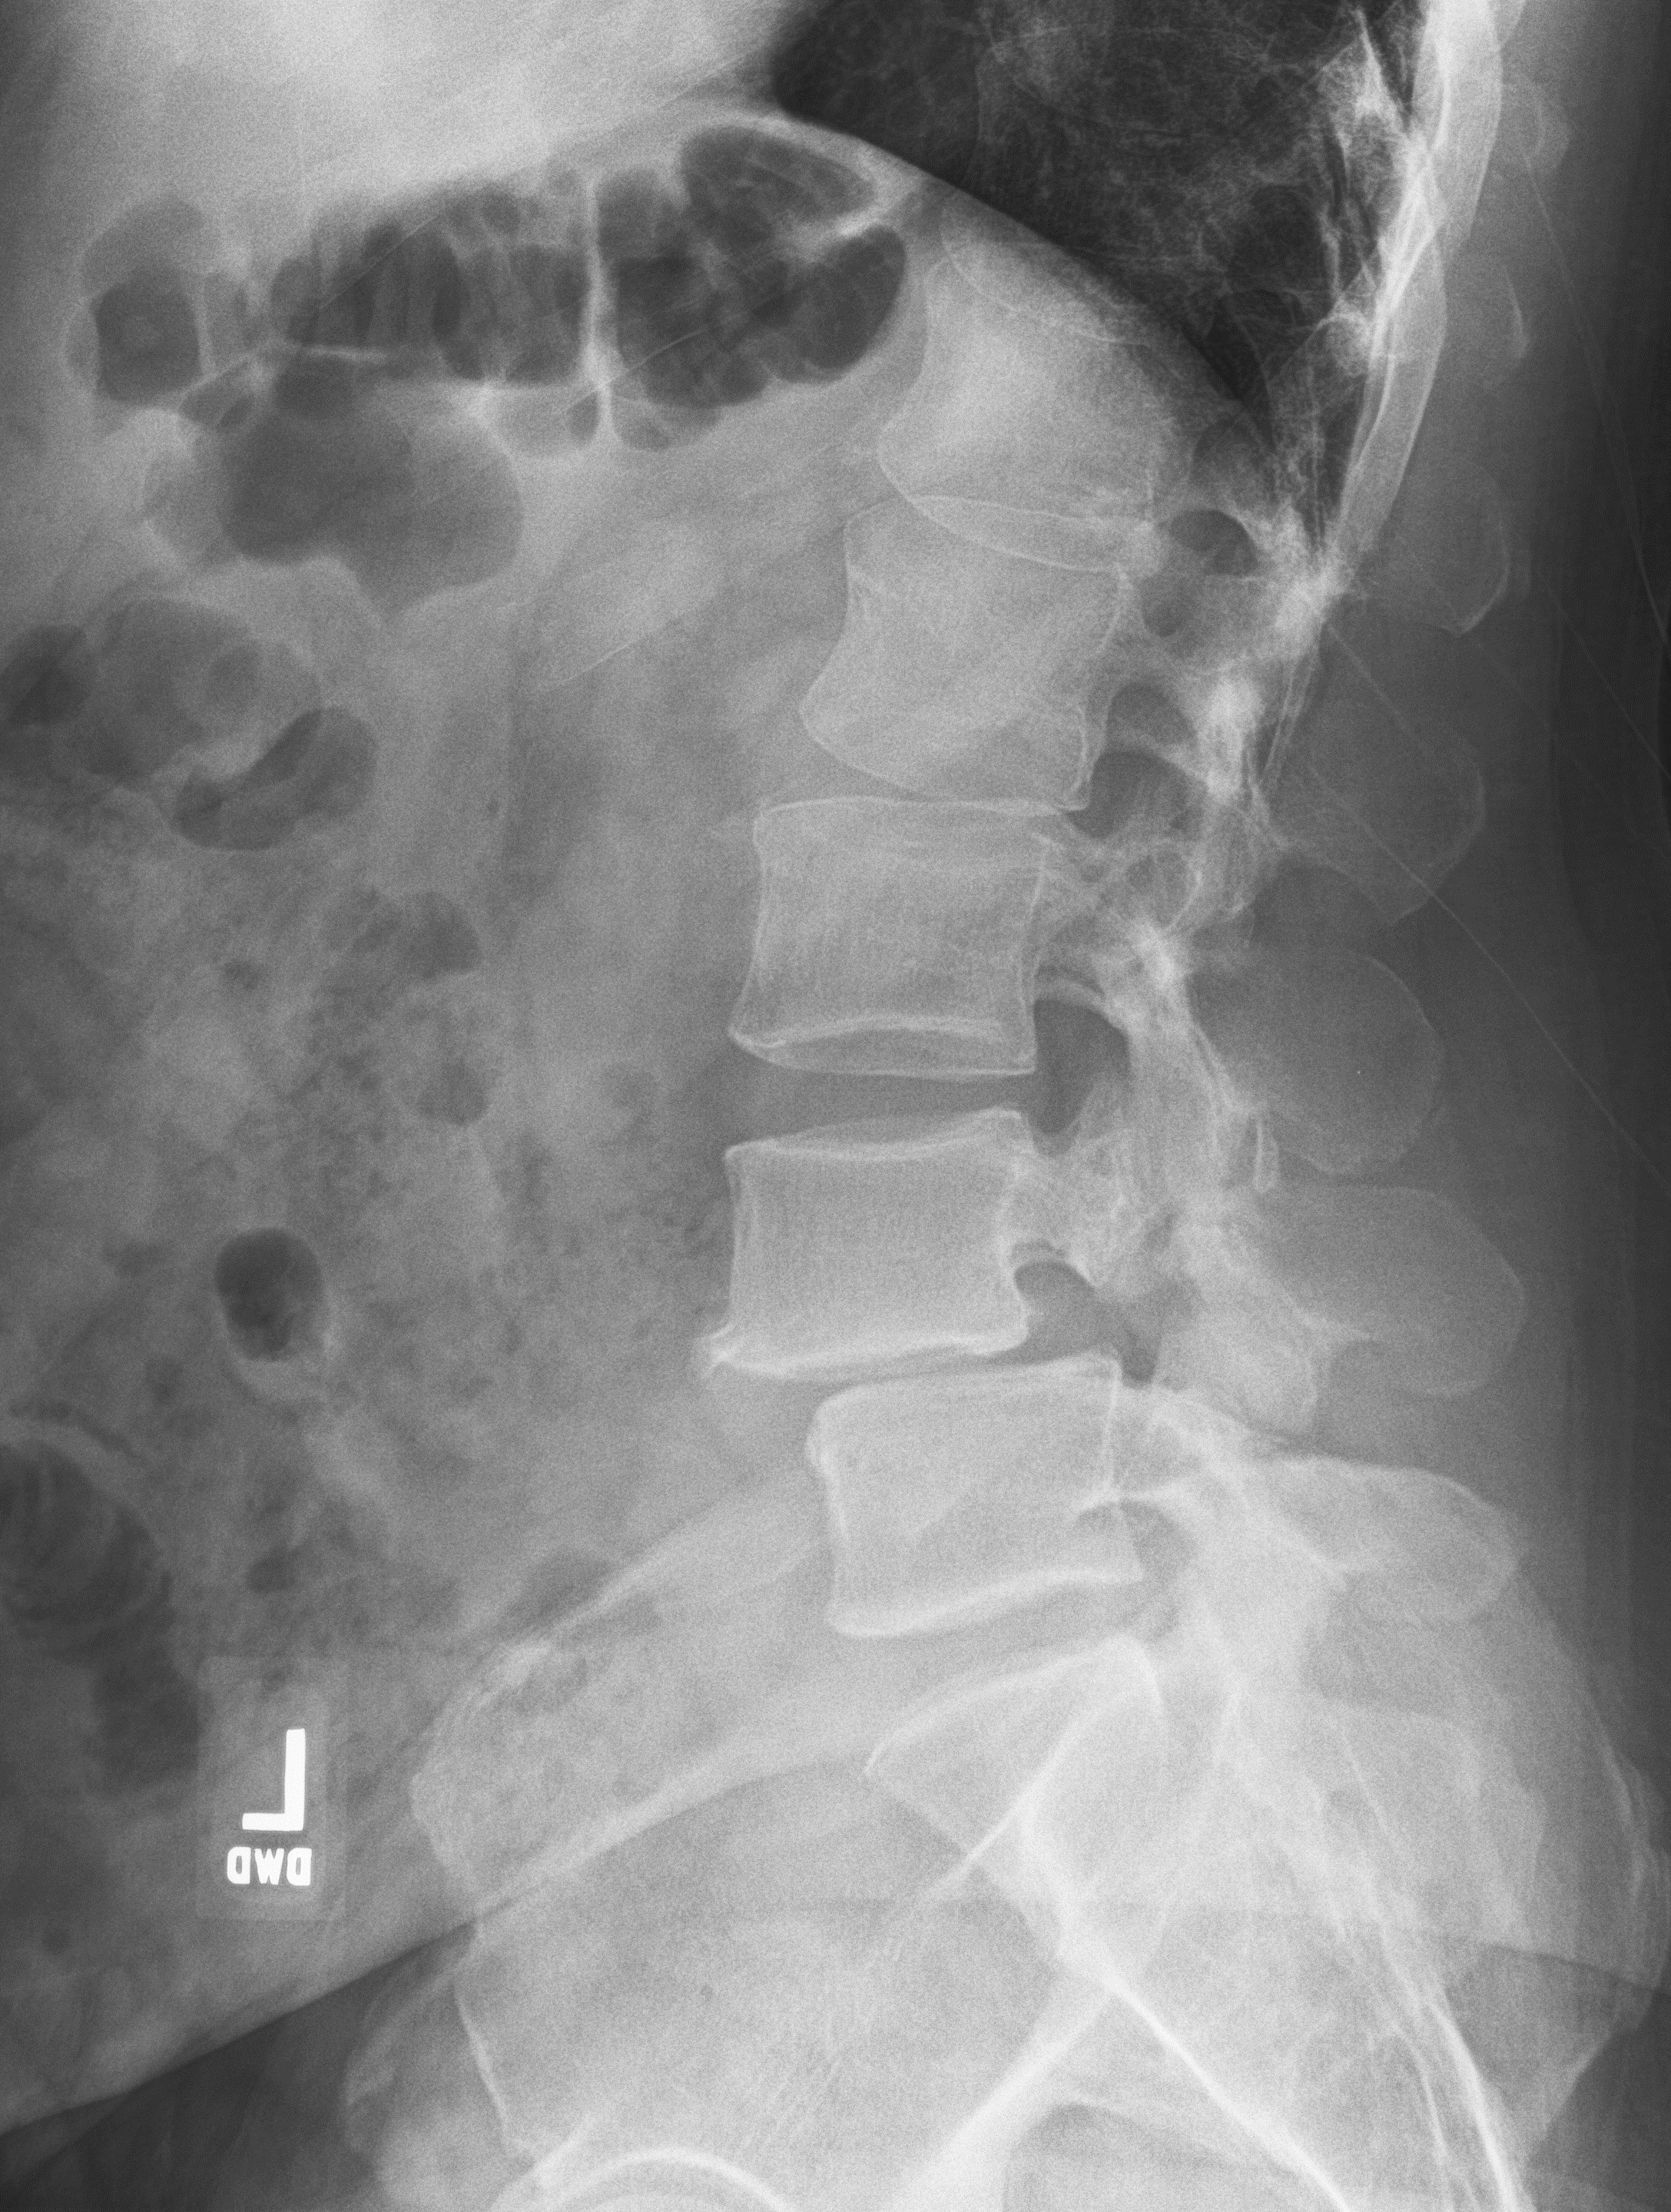

It was there that Hepler was diagnosed with severe disk degeneration and slippage between the vertebrae (spondylolisthesis). The culprit: Age-related wear and tear between the discs and small joints in his lower spine.

In Hepler’s case, the spinal column had shifted eight millimeters out of alignment and his pain level was constantly between a five and 10.

Bennett recommended a new procedure in Winston-Salem, North Carolina, known as a lateral lumbar interbody fusion (XLIF).

This minimally invasive procedure only requires a small incision on the patient’s side, hence the word “lateral” in the name, as well as one or two small incisions on the back. From there, Bennett uses imaging and nerve monitors to guide his surgical instruments to reach the lower spine, or lumbar. At that point, he removes the diseased disc and replaces it with a titanium spacer implant to help improve the alignment of the spine and to take pressure off any nerves that have been pinched.